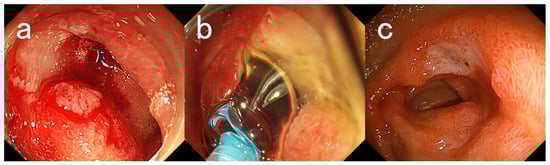

2. Case Descriptions